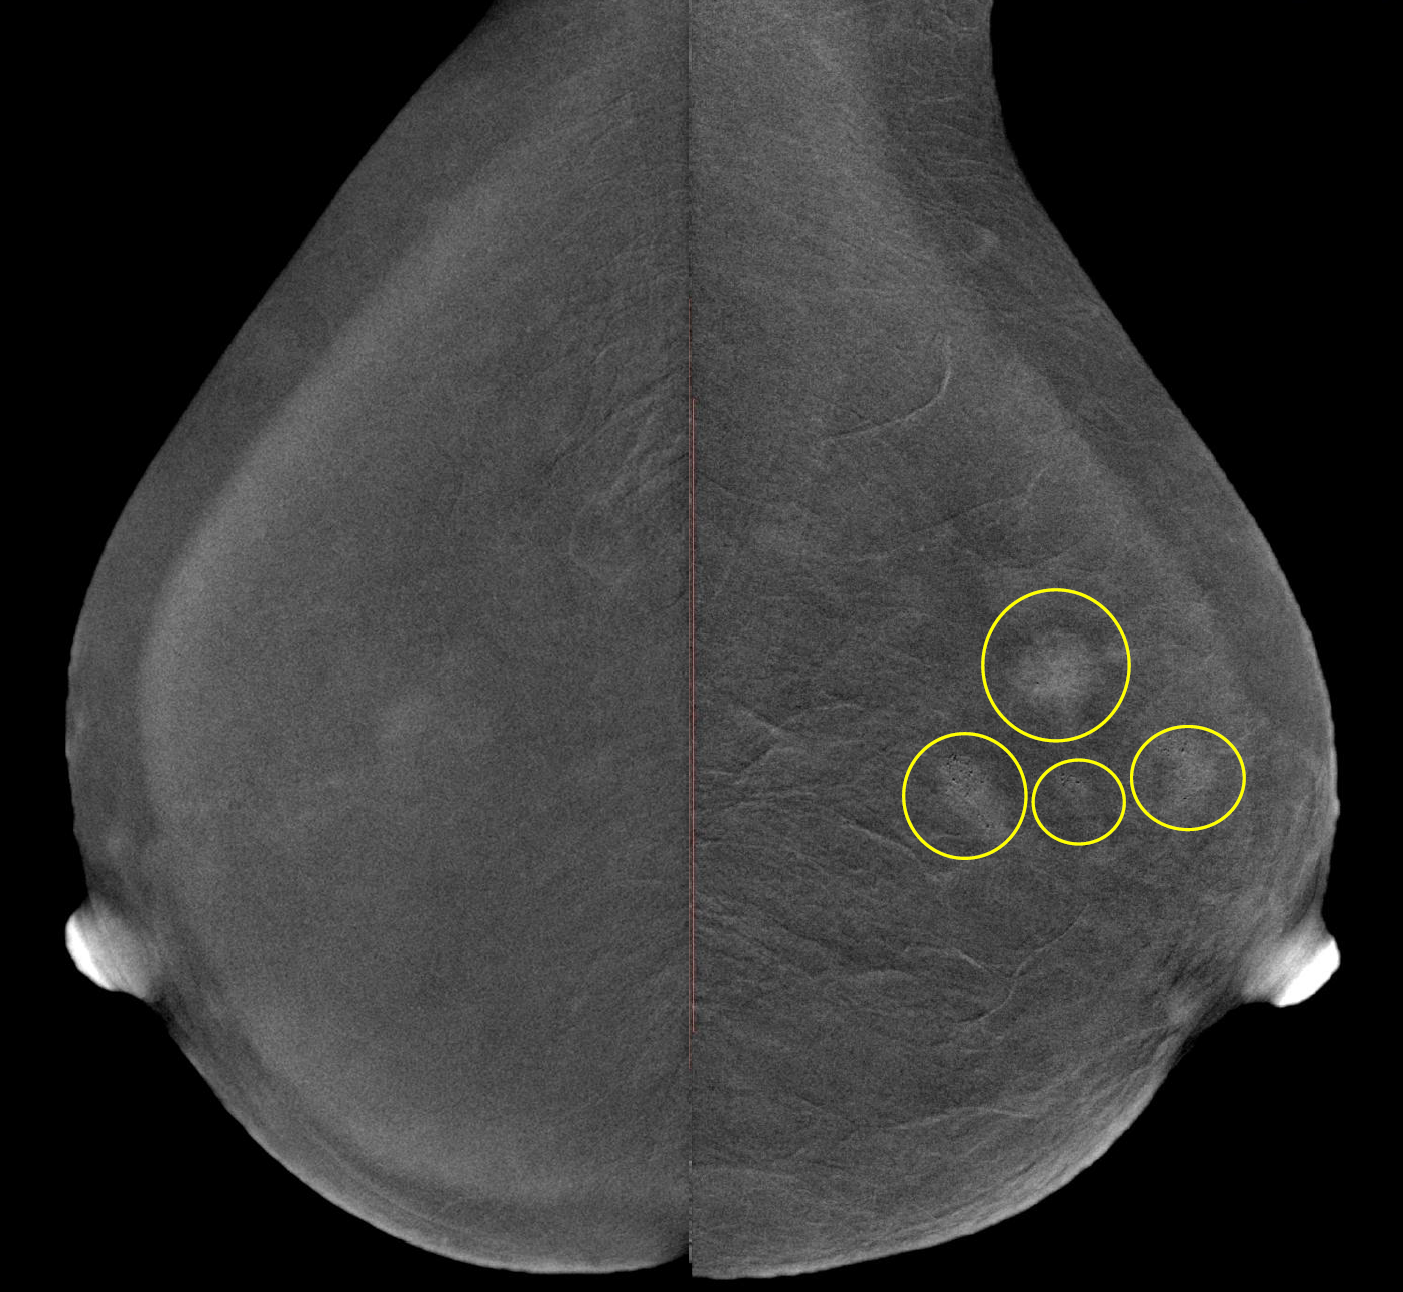

В зависимости от высоты устройства достигается коэффициент геометрического увеличения объекта исследования 1.5х, 1.8х или 2.0х.

Метод прицельной маммографии с увеличением применяется для более детального исследования определенной области молочной железы. Он отличается высокой точностью диагностики. В отличие от обычной маммографии, которая предоставляет более общую информацию о состоянии молочных желез, прицельная маммография с увеличением позволяет получить точные данные о процессах, происходящих в тканях, благодаря методу компрессии конкретного участка.